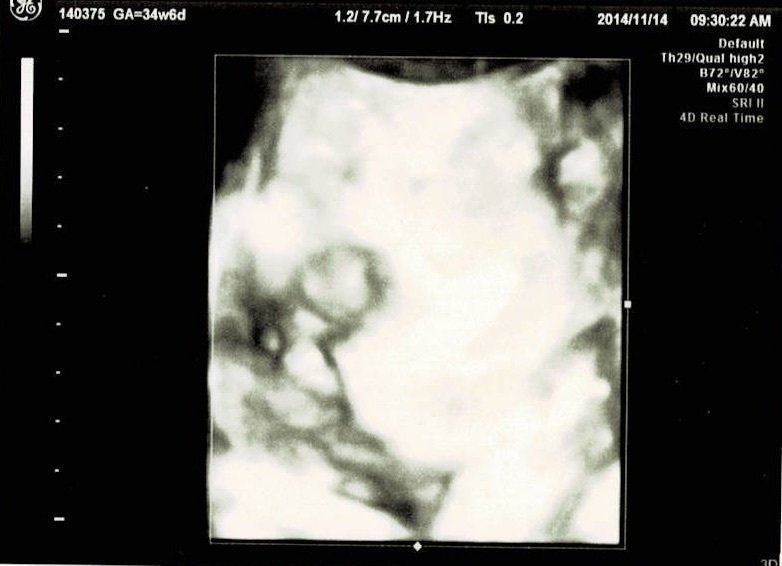

妊娠34週目エコー写真 妊娠後期検査 やっと性別確認

このころ、仕事では有給取得後に産休へ入りました。だんだんと産むことへの不安が大きくなり、連日ネットで情報チェックの日々。この日は妊娠後期検査がありました。溶連菌検査と不規則性抗体のチェックです。赤ちゃんは「身持ちが固い」と先生に言われるくらい股間を見せてくれませんでしたが、この時にやっと性別が発覚。夫婦で感じていた通りの性別だったので、「親ってそういうの分かるのかな?」という話題に。